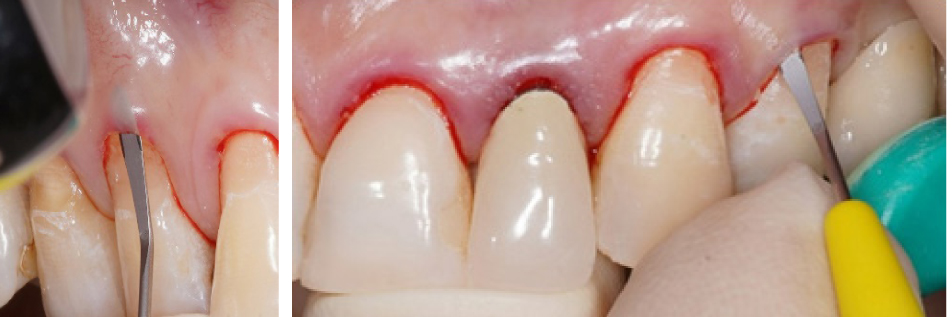

Вначале проводилась антисептическая обработка полости рта 0,05%-м раствором хлоргексидина биглюконата, аппликационная и инфильтрационная анестезии. Затем выполнялись разрезы в области десневой борозды (сулькулярные) через каждую зону рецессии микрохирургическим лезвием с сохранением кончиков десневых сосочков (рис. 2), отслаивание полнослойных лоскутов с помощью микрохирургического распатора. Далее производился забор свободного десневого трансплантата с неба с последующей его внеротовой деэпителизацией и наложением на зону забора параллельных и перекрестных горизонтальных обвивных швов (рис. 3). Позиционирование и фиксация трансплантата в принимающем ложе, ушивание раневой поверхности швами Аллена (рис. 4). Даны рекомендации по послеоперационному ведению: полоскания 0,05%-м раствором хлоргексидина биглюконата 2 раза в день в течение 2 недель, назначены противовоспалительные и обезболивающие лекарственные препараты (НПВС). Повторная явка через день. Швы снимались на 7–10-е сутки. Контрольные осмотры проводились через 3 и 6 месяцев, 1, 2 и 3 года соответственно, оценивалось состояние мягких тканей в области хирургического вмешательства и степень закрытия рецессий десневого края.

Рис. 3. Забор свободного десневого трансплантата с нёба (а) и его деэпителизация (б)